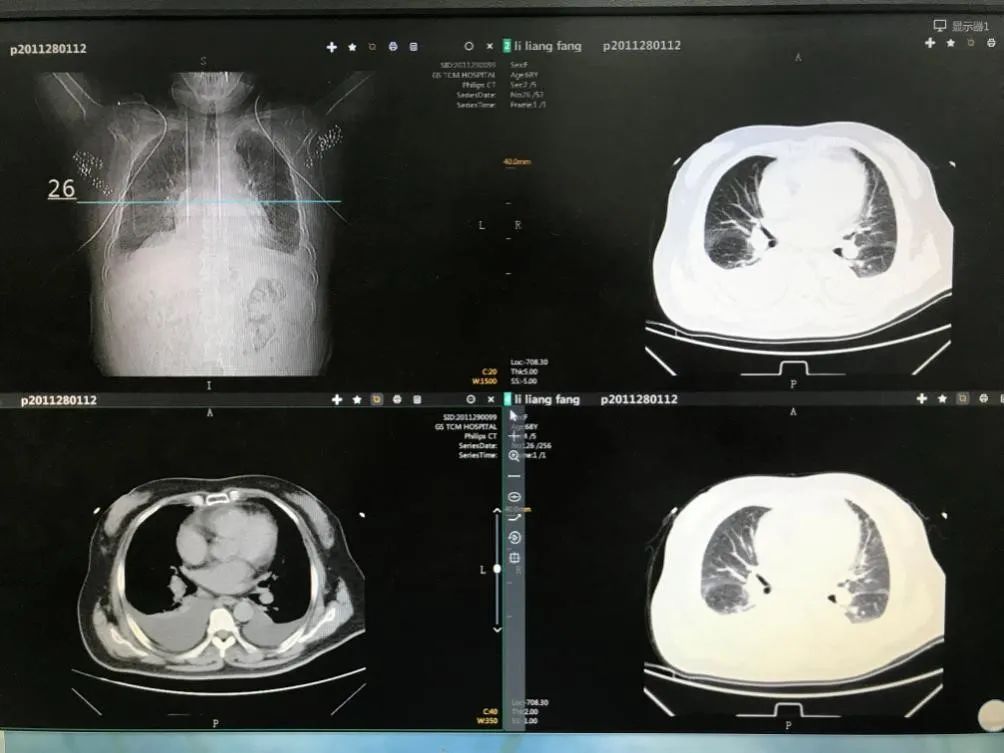

治疗前胸部CT